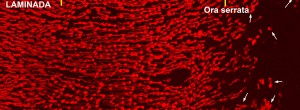

Update on Geographic Atrophy in Age-Related Macular Degeneration.